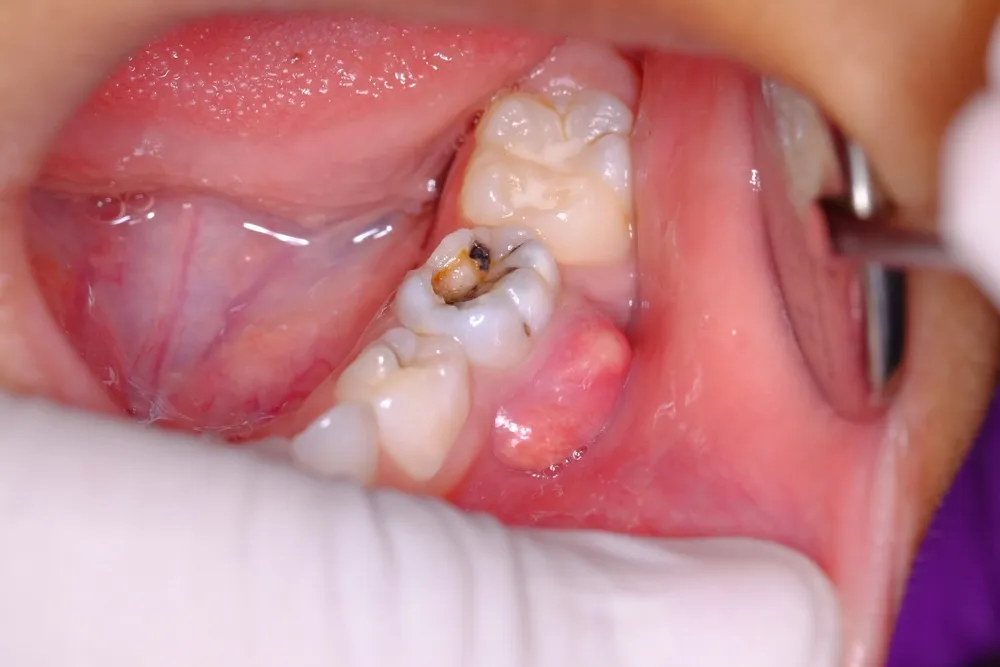

- Những đốm màu trắng đục, đen hoặc nâu là dấu hiệu của tổn thương men răng3. Đây là giai đoạn khởi phát của sâu răng. Nếu không được điều trị kịp thời sẽ phát triển thành lỗ sâu rõ rệt.

Khi răng vĩnh viễn của trẻ bị sâu tiến triển, mức độ đau và các triệu chứng trở nên rõ rệt hơn. Lúc này, vi khuẩn đã ăn mòn cấu trúc men răng và ngà răng. Thông qua đó tạo ra những lỗ sâu với các kích thước khác nhau. Đau răng trở nên thường xuyên hơn và dữ dội hơn, đặc biệt là vào ban đêm.

Đến giai đoạn sâu răng nặng, vi khuẩn đã tấn công sâu vào tủy răng. Từ đó gây viêm tủy hoặc hoại tử tủy. Răng vĩnh viễn của trẻ bị sâu lúc này đã mất đi phần lớn cấu trúc. Khi đó chúng có thể bị gãy hoặc vỡ do vi khuẩn tiếp tục phá hủy mô răng. Đây là giai đoạn nghiêm trọng nhất của bệnh sâu răng. Nó có thể dẫn đến các biến chứng như viêm tủy, viêm chóp răng. Thậm chí là nhiễm trùng toàn thân nếu không được điều trị kịp thời.